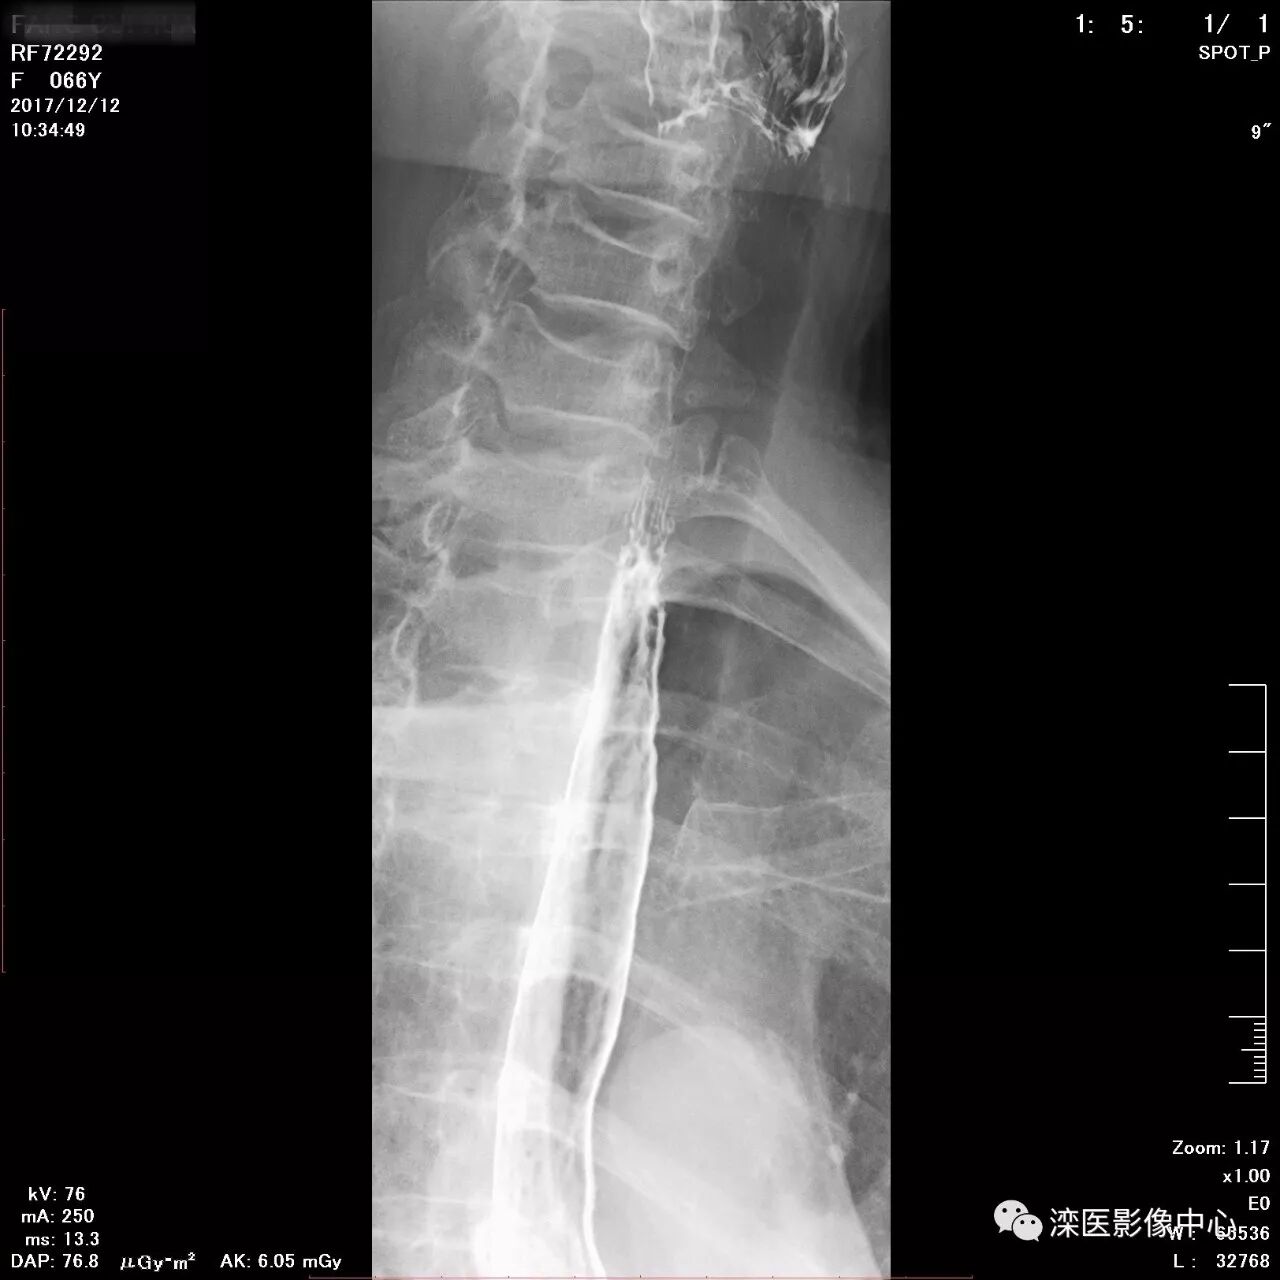

正位,显示食管、贲门及喉咽部的粘膜像)

(左前斜位,显示食管、贲门的粘膜像

(右前斜位,显示食管、贲门的粘膜像)

(以上图像是患者立位+卧位,通过变换体位,多角度显示了贲门胃底、胃体、胃大弯、胃小弯、胃窦、幽门及十二指肠球部、降部、水平部、升部的粘膜像和充盈像。本例患者女性,66岁,此次检查可以清晰显示胃小区结构,检查中发现患有慢性胃炎、胃下垂、十二指肠降部憩室)